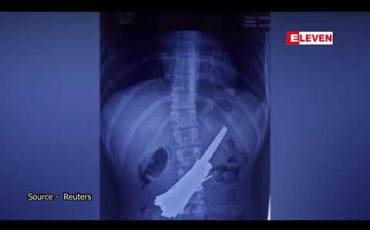

Embedded thumbnail for အိန္ဒိယ ဆယ်ကျော်သက်တစ်ဦး၏ ဗိုက်ထဲမှ အိမ်ရိုက်သံ အချောင်း ၃၀ ကို ဆရာဝန်တွေ ဖယ်ရှားခဲ့ရ

အိန္ဒိယနိုင်ငံ မြောက်ပိုင်း အူတာပရာဒေ့ရှ်ပြည်နယ်မှာ ဆရာဝန်တွေက အသက် ၁၈ နှစ်အရွယ် ယောကျ်ားလေးတစ်ဦးရဲ့ ဗိုက်ထဲကနေ အိမ်ရိုက်သံတွေများစွာနဲ့...